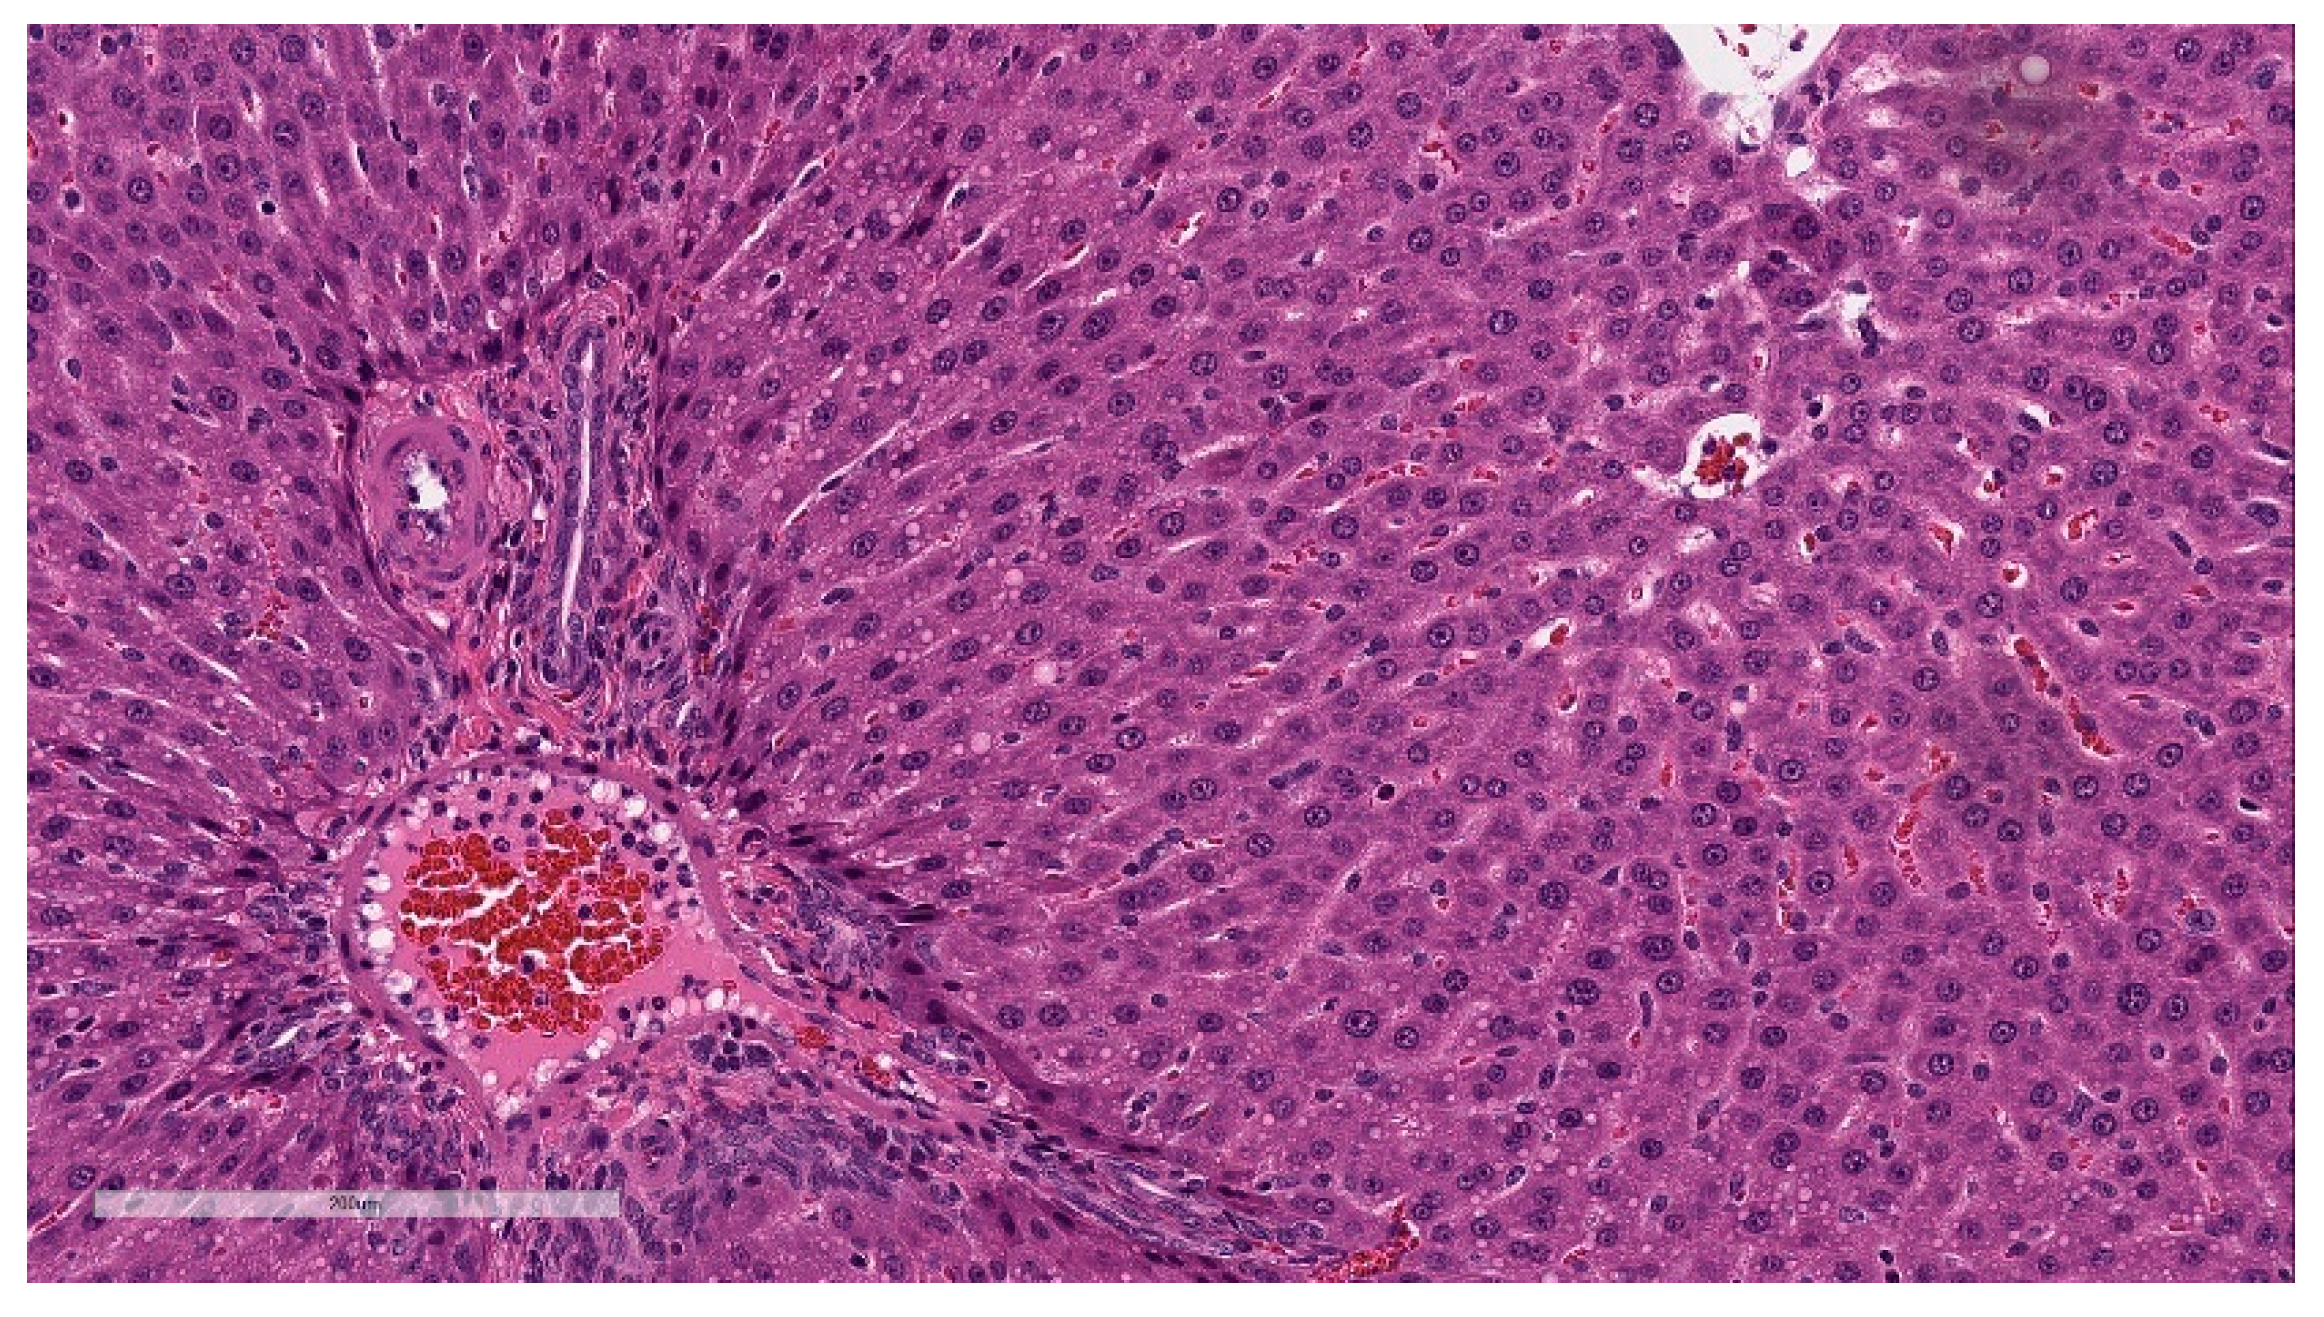

Minimal hepatocellular vacuolation was evident in portal hepatocytes (Figure 7). This was not associated with hepatocyte degeneration or necrosis or with biochemical alterations in hepatocyte injury biomarkers (AST and ALT) and was considered secondary to the distribution of LNP lipids in the hepatocytes [33]. This finding was fully resolved at the end of the 3-week recovery phase.

Figure 5. Histopathologic features of Injection site inflammation and edema at the end of the dosing phase. (a) Injection site sections of BNT162b2 (V9) treated animals euthanized 2 days after the third dose (Day 17) showed inflammatory cells admixed with abundant pale eosinophilic fluid (edema) infiltrating and expanding subcutaneous tissue and connective tissue of skeletal muscle. (b) Higher magnification of (a) showing.